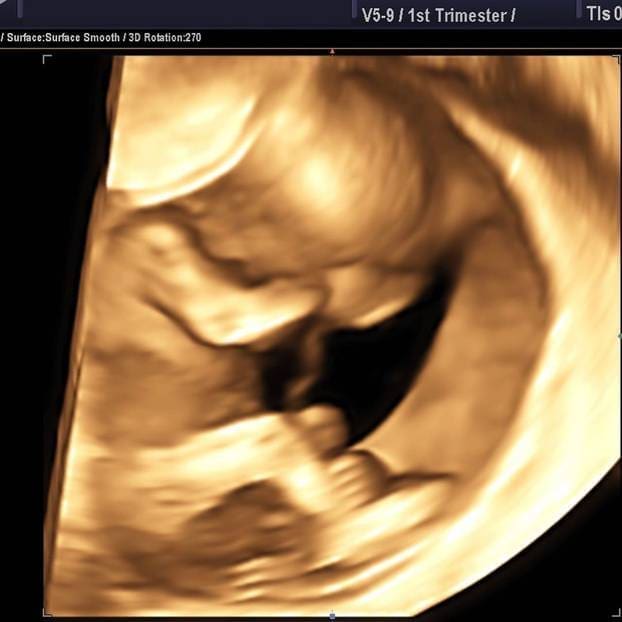

Napokon je došao trenutak da vam otkrijemo slatku tajnu i da beba ima prvu foto uspomenu na rast u maminom trbuščiću. Danas slavimo 15 tjedana u nadi da će sljedećih 25 proći ovako lijepo i sigurno za nas. Poželite nam sreću - napisala je presretna Maja poručujući da će ona i suprug Nenad postati bogatiji za jednog članak obitelji.

"Jedan od najčudesnijih trenutaka u mom životu. Kad prvi puta vidiš ovako bebu, osjećaj je neopisiv", napisala je 41-godišnjakinja uz objavljenu fotografiju s ultrazvučnog pregleda koja je snimljena 19. rujna.

"Beba udobno sjedi, nismo vidjeli spol. Ovo je bio 12. tjedan... Što mislite je li cura ili dečko? - upitala je Maja svoje pratitelje.